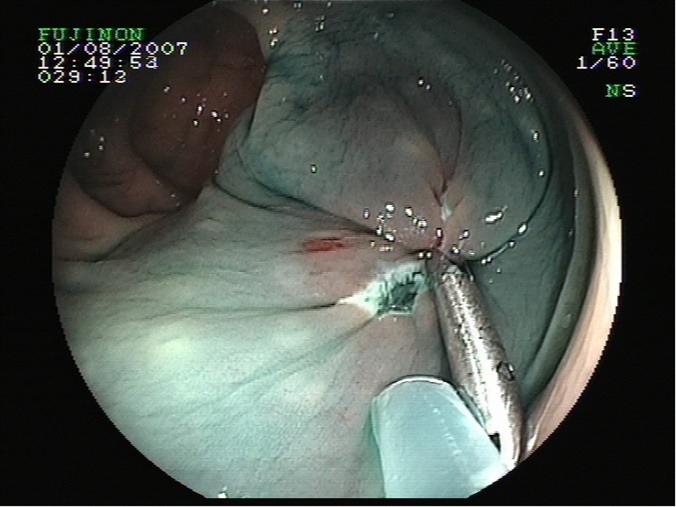

Sutura con clips